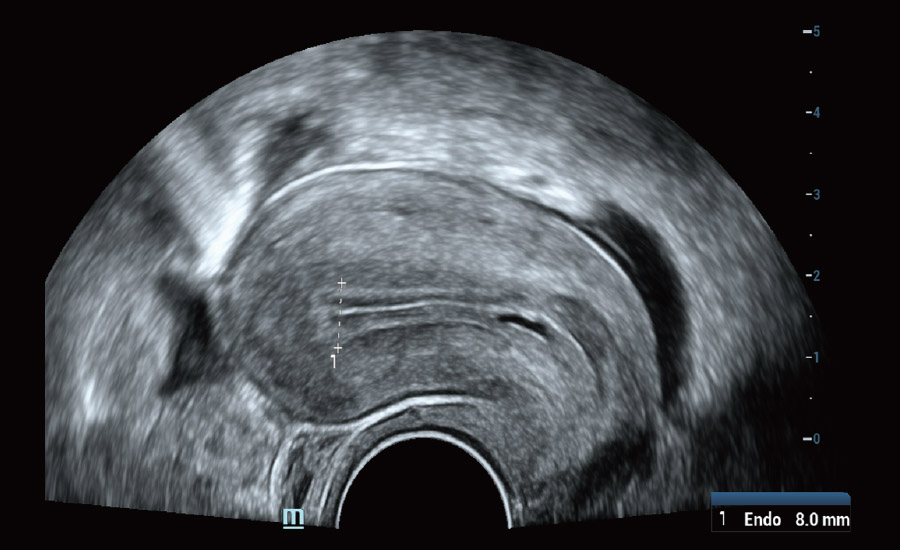

UMA ā Fluxo uterino e endometrial

A tecnologia inovadora elimina as limita??es das tradicionais imagens com Doppler. Com resolu??o espacial e sensibilidade de fluxo ultra-altas, permite a detec??o de perfus?es de fluxos muito sutis e lentos, ampliando assim a aplica??o clĆnica da avalia??o qualitativa e quantitativa do ultrassom no cĆ©rebro fetal, rins, placentas, endomĆ©trios, ovĆ”rios etc.

UMA (angiografia ultramicroscĆ³pica)

- Cuidando da saĆŗde da mulher com solu??es em ginecologia e uroginecologia

Ginecologia